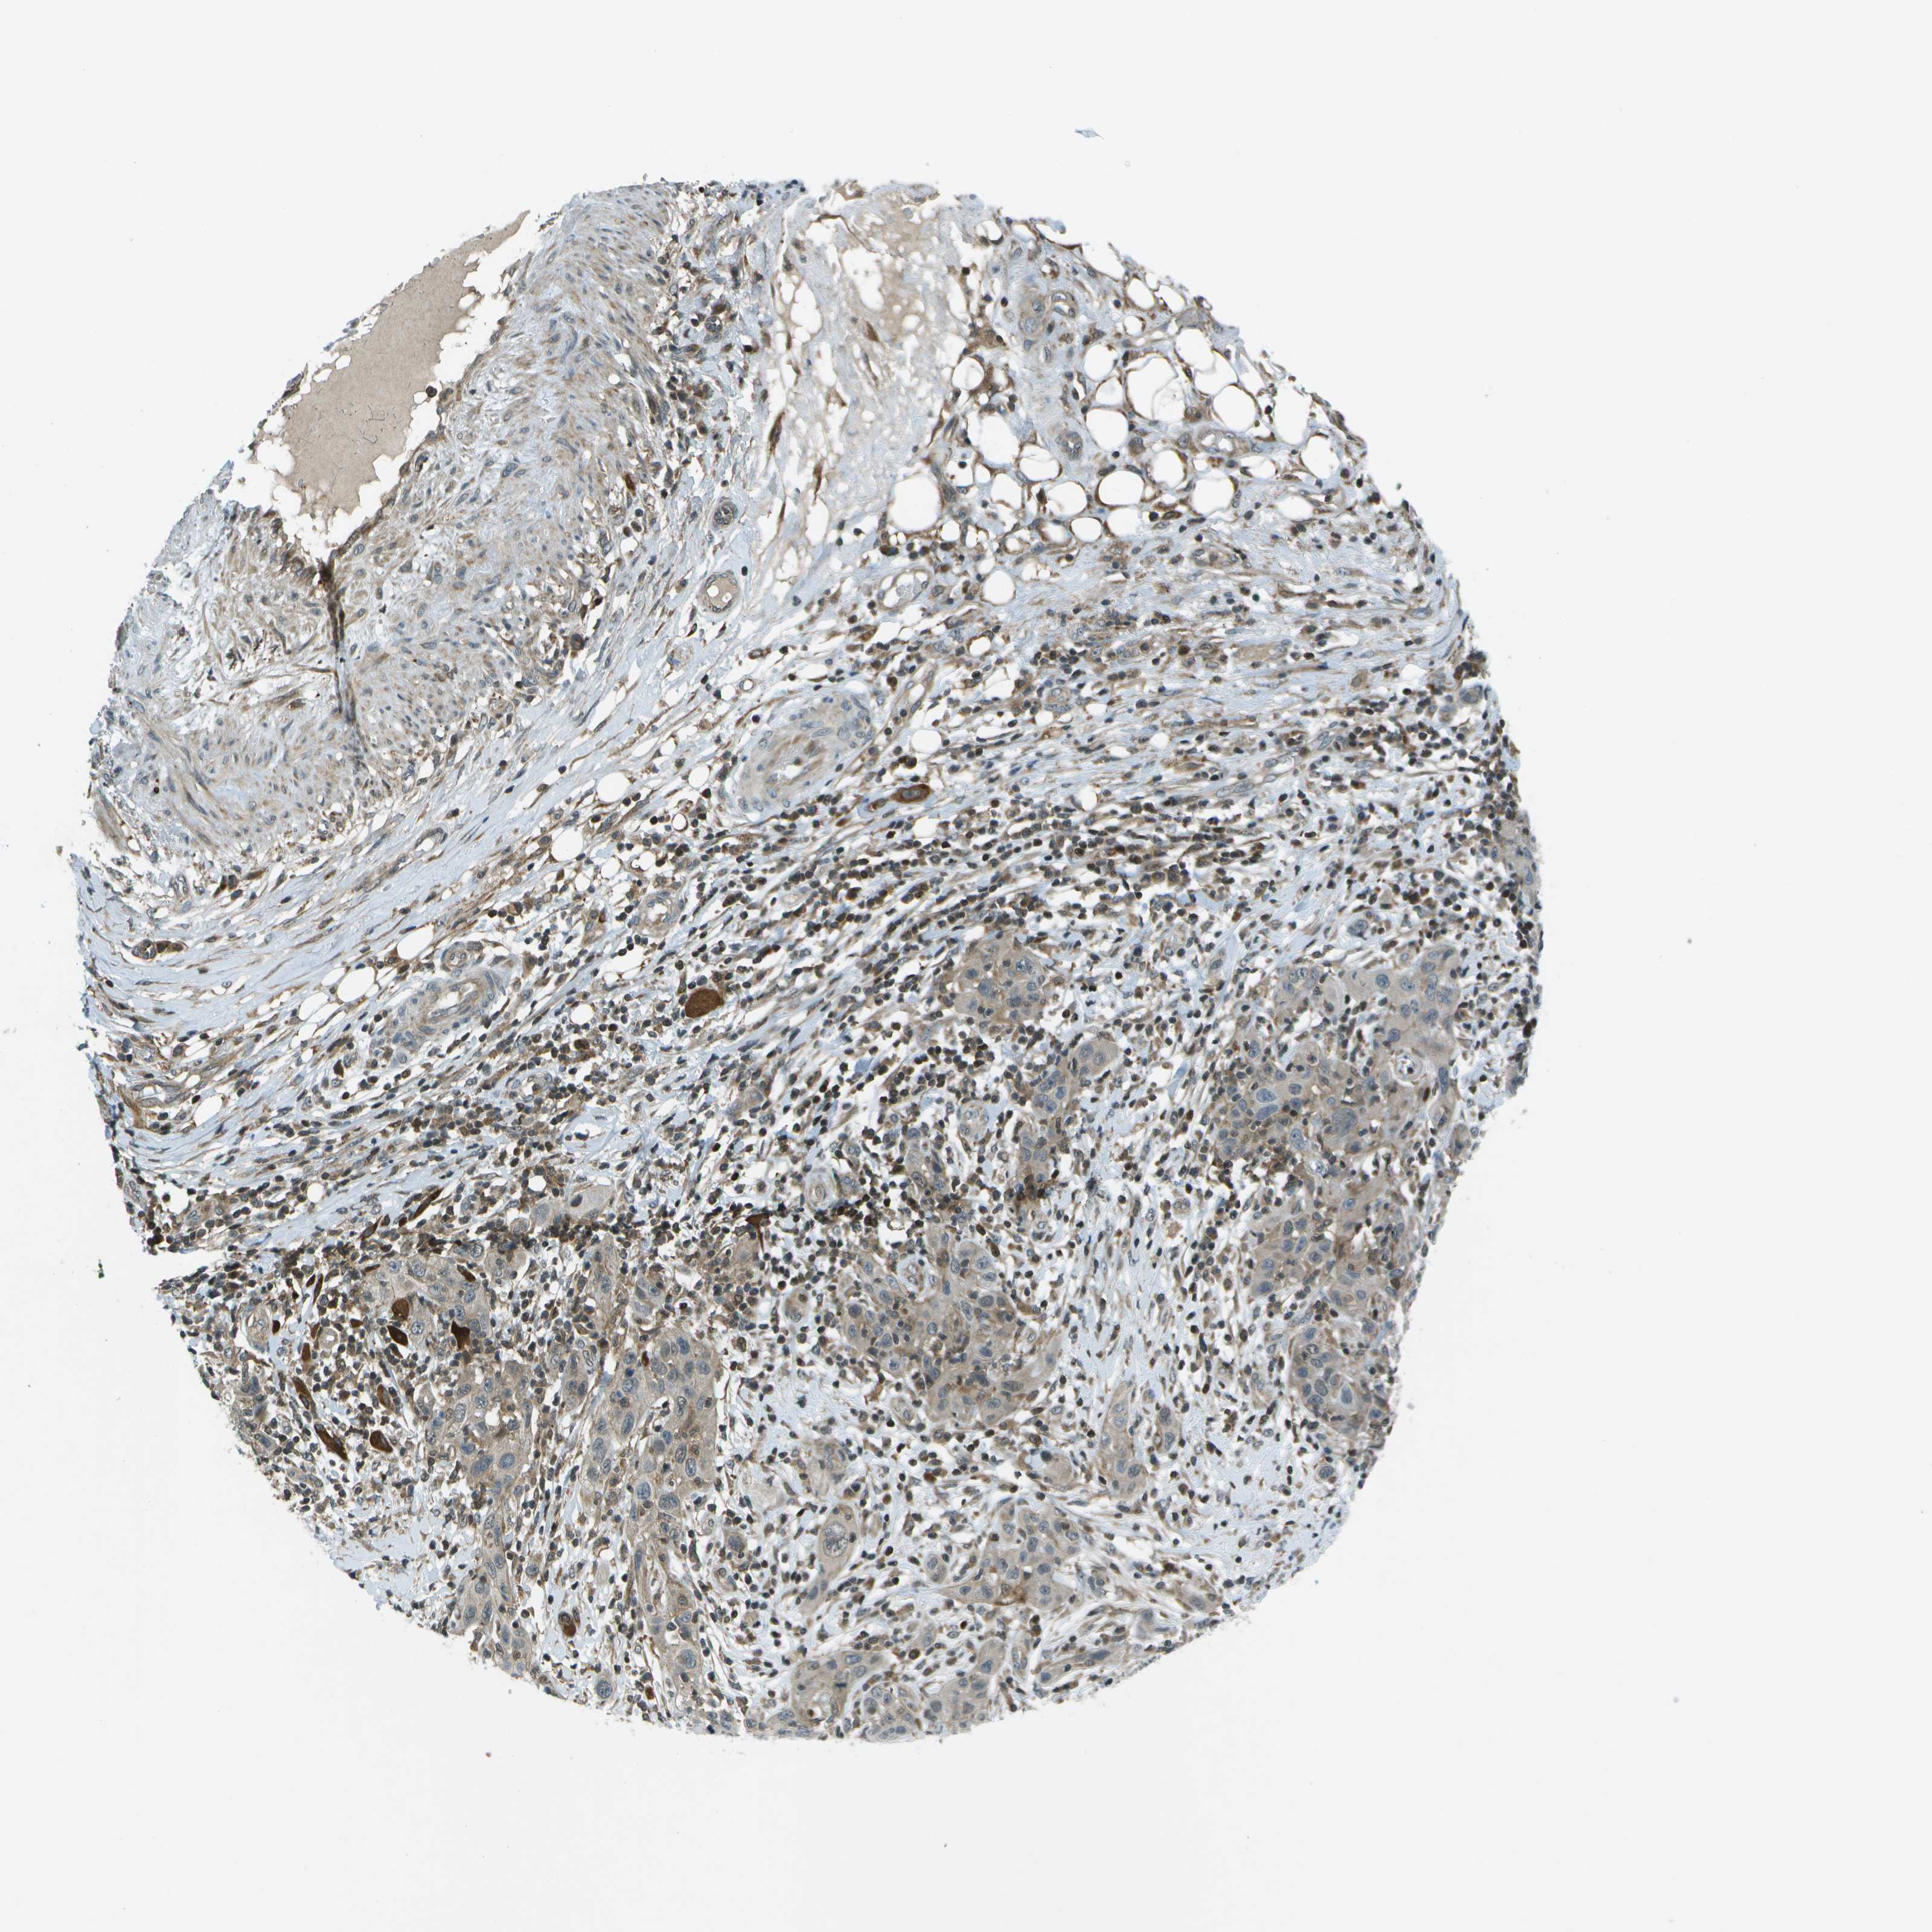

SKIN CANCER - Protein expressioni

A mouse-over function shows sample information and annotation data. Click on an image to view it in a full screen mode. Samples can be filtered based on level of antibody staining by selecting one or several of the following categories: high, medium, low and not detected. The assay and annotation is described here.

Each image is clickable and will lead to virtual microscopy that enables deeper exploration of all samples and also displays staining intensity scores, fraction scores and subcellular localization as well as patient and tissue information for each sample.

Antibody HPA016830

Staining

High

Intensity

Strong

Quantity

>75%

Location

Nuclear

Squamous cell carcinoma in situ, NOS

Squamous cell carcinoma, NOS

Squamous cell carcinoma, metastatic, NOS

Basal cell carcinoma

Adnexal tumor, benign